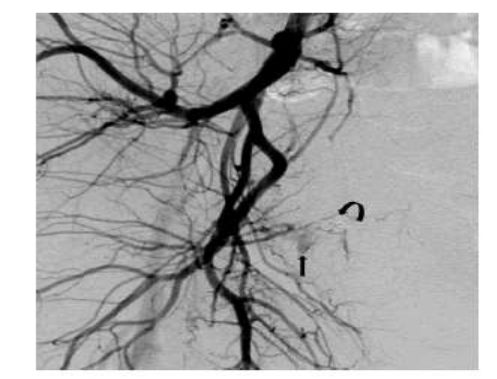

Jacques et al. [25] reported a 27-year-old year old null gravid lady, who was on warfarin anticoagulation in view of her having a mechanical tricuspid valve and underlying congenital heart disease, who manifested with sudden onset of profuse vaginal bleeding despite being on continuous oral contraceptive pills. She had been admitted on three separate occasions over a period of 3 months for the management of menorrhagia and overall, she had been transfused with 25 units of blood. During her initial assessment, she received high-dose intravenous oestrogen successfully and she was discharged home on oral contraceptive pill. Her vaginal bleeding recommenced many weeks subsequently and upon her admission she had examination of her pelvis which demonstrated a bluish mass at the apex of her vagina which was suspected to be an arteriovenous malformation (AVM). In view of the bleeding with utilization of hormones as well as a question of a possible mass within her vagina on examination, she had an MRI scan of pelvis which demonstrated blood products at varying stages that had expanded the endometrial cavity without any definite cause identified as well as no arteriovenous malformation (AVM) was identified (see figure 12). She underwent dilatation and curettage (D&C) as well as placement of levonorgestrel intra-uterine device. Pathology examination of the curetting demonstrated benign endometrium that had progestin effect. She was discharged home and she was well for one week until her intra-uterine device (IUD) was expelled and she re-commenced bleeding again from her vagina for which she was initially managed by means of placement of an etonogestrel implant. She was re-admitted one week later due to her profuse bleeding from her vagina that required blood transfusion. An attempt was made to treat her with leuprolide which did not produce any successful effect. She was on warfarin treatment, which was reversed, and she underwent laparoscopic hysterectomy. There was no suspicion of AVU during the operation. Pathology examination of the surgical specimen did not demonstrate any abnormalities within her uterus, cervix, and fallopian tubes. She was well for 4 weeks after her operation but she suddenly re-manifested with bleeding from her vagina that required utilization of wall suction for visualization of her vagina and cervix and the bleeding was observed at the right side of her vaginal cuff. Her vagina was packed with gauze and she had CT angiogram which demonstrated active arterial bleeding within the right side of the apex of her vagina which was suggestive of an AVM (see figure 13). She was transfused with 2 units of packed red blood cells and prothrombin complex concentrate (PCC) was used to reverse her anti-coagulation. She had angiogram which revealed active extravasation from her right uterine artery with an artery to venous fistula (see figure 14). Two coils had to be placed proximal to the part of the uterine vessel which had vaginal branches, and this emanated in successful obliteration of the AVMU as well as cessation of her vaginal bleeding. She was recommenced on heparin drip as well as warfarin pursuant to her operation; nevertheless, on the day her INR reached therapeutic range, she re-started having profuse vaginal bleeding again. PCC was utilized to reverse her anti-coagulation. She had right internal iliac arteriogram which demonstrated abnormal blush as well arterio-venous fistula (AVF) within the same region as before, near the previously embolized uterine artery (see figure 15). Embolization of her right uterine artery was undertaken with glue. Catheterization of multiple branches of the artery did not demonstrate any extravasation of contrast. She was recommenced on warfarin as well as on heparin drip subsequently until her INR had reached therapeutic range. She was subsequently discharged, and she did not develop any further bleeding from her vagina. At her 6-week post-operative follow-up assessment, her examination demonstrated a well healed, and intact, cuff of her vagina. A lesson that has been learnt from this case report is that if an AVM develops with bleeding following hysterectomy for AVM, selective angiography and embolization could be undertaken to obliterate the AVM and to stop the bleeding.

Figure 15: Right internal iliac artery catheter angiography done at the time of the second arterial embolization by interventional radiology. Images abnormal blush/ AV fistula (arrow) in the same location to previous embolization site (curved arrow showing the coil). Near stasis of the right uterine artery was noted which was further embolized completely with glue. Reproduced from: [25] Jacques L, Lund M, Baruah D. Uterine Arteriovenous Malformation: A Rare Cause Vaginal Hemorrhage after hysterectomy. Gynecology & Obstetrics Case Report. 2016; 2(2): 1 – 4. doi:10.21767/2471-8165.1000029 https://gynecology-obstetrics.imedpub.com/uterine-arteriovenous-malformations-a-rare-cause-of-vaginal-hemorrhage-after-hysterectomy.pdf https://gynecology-obstetrics.imedpub.com/uterine-arteriovenous-malformations-a-rare-cause-of-vaginal-hemorrhage-after-hysterectomy.php?aid=11196